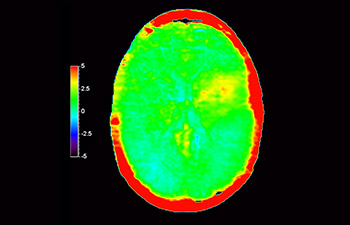

In a society where neurological disorders represent a heavy burden, Philips is committed to provide superb diagnostic clarity and treatment guidance for all patients. Today, although MR is the gold standard in neuro oncology imaging, its accuracy in tumor grading and treatment follow up assessment can be further improved. 3D APT (Amide Proton Transfer) is a unique, contrast-free, brain MR imaging method addressing the need for more confident diagnosis in neuro oncology. 3D APT uses the presence of endogenous cellular proteins, to produce an MR signal that directly correlates with cell proliferation, a marker of tumoral activity. 3D APT can support trained medical professionals in differentiating low grade from high grade gliomas and, in differentiating tumor progression from treatment effect1.